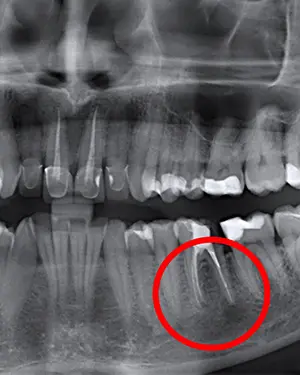

Če občutite bolečino ali otekanje zoba, ki je že endodontsko zdravljen, je potrebno poiskati pomoč stomatologa. Stomatolog bo v tem primeru naredil RTG posnetek tega področja (zoba in okoliške kosti) ter opravil klinični pregled, kakor bi odločil, ali je potrebno opraviti apikotomijo. Koreninski kanali so zelo kompleksni, še posebej na vrhu korenine. Včasih po endodontskem posegu zaostanejo infektivni ostanki znotraj kanala. To lahko privede do kasnejše ponovne okužbe korenine in potrebe za apikotomijo. Pri apikotomiji se odstrani vrh korenine skupaj z vnetnim in inficiranim tkivom, na kar se s polnjenjem kanala zapečati vrh korenine. Apikotomija je danes vse bolj pogost poseg, saj pacientom omogoča ohranjanje zob, katere ni možno zdraviti z endodontsko terapijo in katere bi drugače morali izpuliti. Šteje se za majehn kirurški poseg, traja pa od 30 do 60 minut, odvisno od tega za katero regijo in zob se gre. Posegi na sprednjih zobeh so praviloma krajši, med tem ko so posegi na spodnjih kotnikih najdaljši.